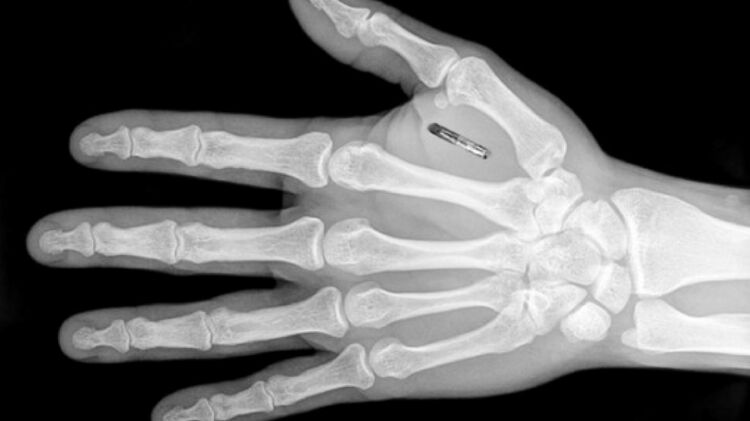

В Швеции компания Epicenter, специализирующаяся на субдермальных микрочипах, продемонстрировала имплант, способный хранить информацию об COVID-паспорте человека.

Сджоблад объяснил, что чипы могут имплантировать либо между большим и указательным пальцами, либо в саму руку чуть выше запястья. Сам микрочип размером с рисовое зерно.